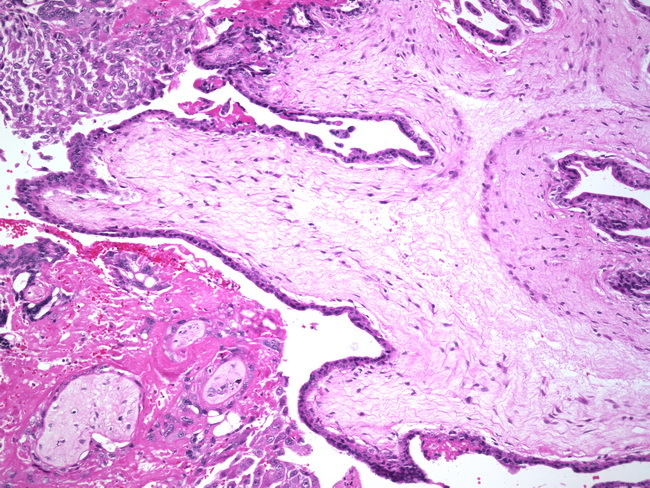

Dx?

Third trimester placenta

(Thinning of trophoblasts, less interstitium, more blood vessels)